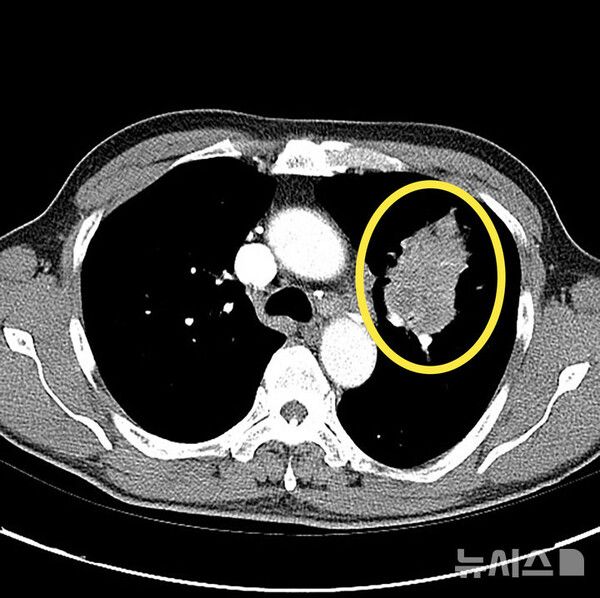

폐암은 초기 증상이 없는 경우가 대부분이고, 일반 감기와 증상이 비슷해 진단이 늦어지는 경우가 많다. 건강검진에서 우연히 결절이 발견돼 추가 검진을 통해 진단 되곤 한다.

15일 의료계에 따르면 폐암은 폐에 비정상적인 암세포가 무절제하게 증식해 종괴(덩어리)를 형성하고 인체에 해를 미치는 것을 말한다. 폐암은 폐에 국한돼 발견되기도 하지만 진행될 경우 반대쪽 폐뿐 아니라 임파선이나 혈액을 통하여 뼈, 간, 부신, 신장, 뇌, 척수 등 온몸으로 전이될 수 있다.

하지만, 최근에는 비흡연자에게서도 폐암 발병이 증가하고 있어 증상이 없고 고위험군이 아니더라도 관심을 기울일 필요가 있다. 간접흡연이나 요리시 발생하는 연기, 라돈·석면 등 발암물질에 노출되는 직업 종사자나 미세먼지 노출시에도 폐암에 걸릴 수 있다. 저선량 흉부 CT(컴퓨터단층촬영)는 폐암 조기 진단에 매우 효과적인 수단으로 만성 폐쇄성 폐질환(CODP)이나 다른 암 병력이 있는 등 고위험군에서는 정기적인 검사가 권장된다. 저선량 CT는 환자에게 노출되는 방사선량을 6분의 1 수준으로 최소화한 장비다.

따라서 고위험군에서는 저선량 CT를 이용한 정기 검진이 매우 중요하다. 결절이 발견된다고 다 암으로 진행되는 것은 아니다. 결절은 암일 수도 있지만 염증, 섬유화, 림프절 비대, 과거 결핵 흔적 등 다양한 원인으로 생길 수 있다. 특히 폐암 고위험군이라면 호흡기알레르기내과 전문의에게 진료를 받아 정확한 평가를 받는 것이 필요하다.